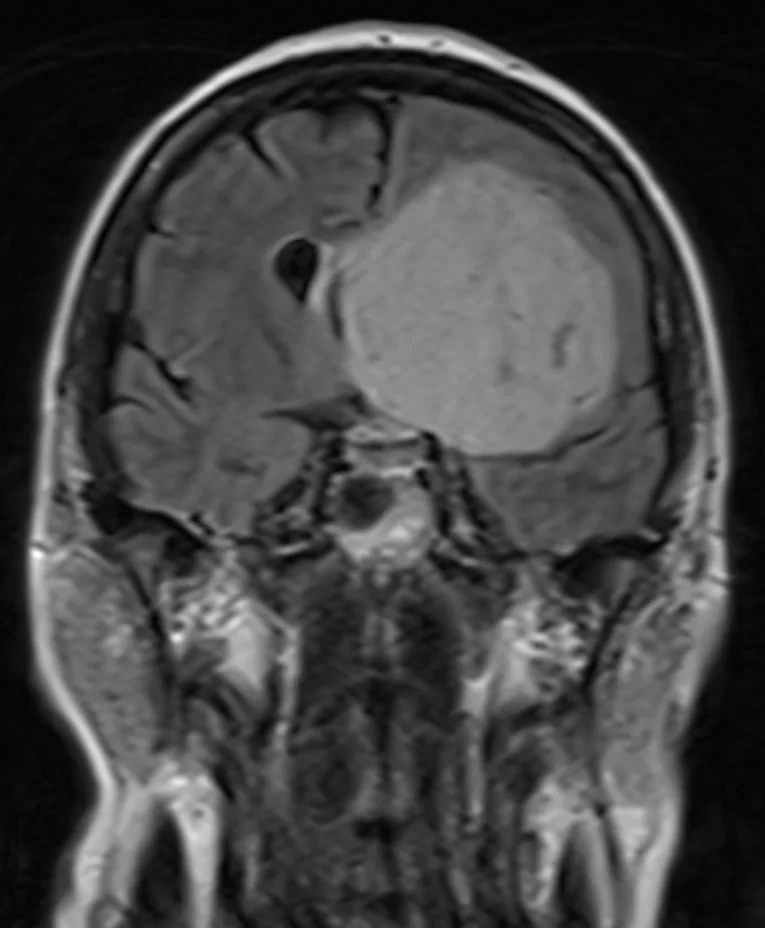

Ο απεικονιστικός έλεγχος με μαγνητική τομογραφία ανέδειξε ευμεγέθη όγκο της πτέρυγας του σφηνοειδούς αριστερά, συμβατό με μηνιγγίωμα.

Πρόκειται για ένα ιδιαίτερα μεγάλο μηνιγγίωμα, στην επικρατούσα πλευρά (αριστερά), το οποίο πίεζε δομές όπως τα οπτικά νεύρα και είχε «ενσωματώσει» σημαντικά αγγεία του εγκεφάλου (αριστερή καρωτίδα και κλάδους της). Όγκοι σαν και αυτόν χρειάζονται υπομονή και καλή μικροχειρουργική τεχνική προκειμένω να παρασκευαστούν και να προφυλαχθούν όλα τα κρίσιμα αγγεία. Η υποχώρηση των συμπτωμάτων ήταν άμεση.